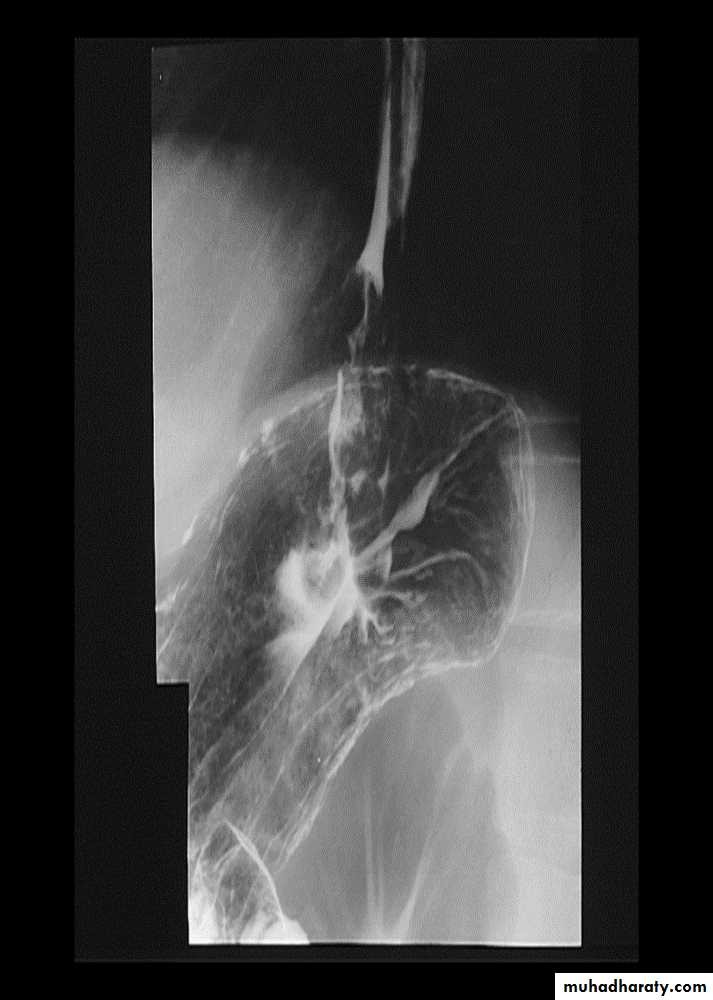

Inflammation and Infection

Gastroesophageal reflux (GERD) is the most common cause of esophagitis.Infectious esophagitis

Candida esophagitis:in patient with an infectious esophagitis due to candida , the barium shows numerous fine erosions & plaques causing shaggy outline of the osophagus due to Candida albicans in immunocompromised patient.

middle year old female with a past medical history significant for HIV/AIDS comes in with complaint of loosing their weight over the past 2 weeks with pain & difficulty on swallowing …. Also feels like food is getting stuck in her throat

What is your diagnosis ??????????